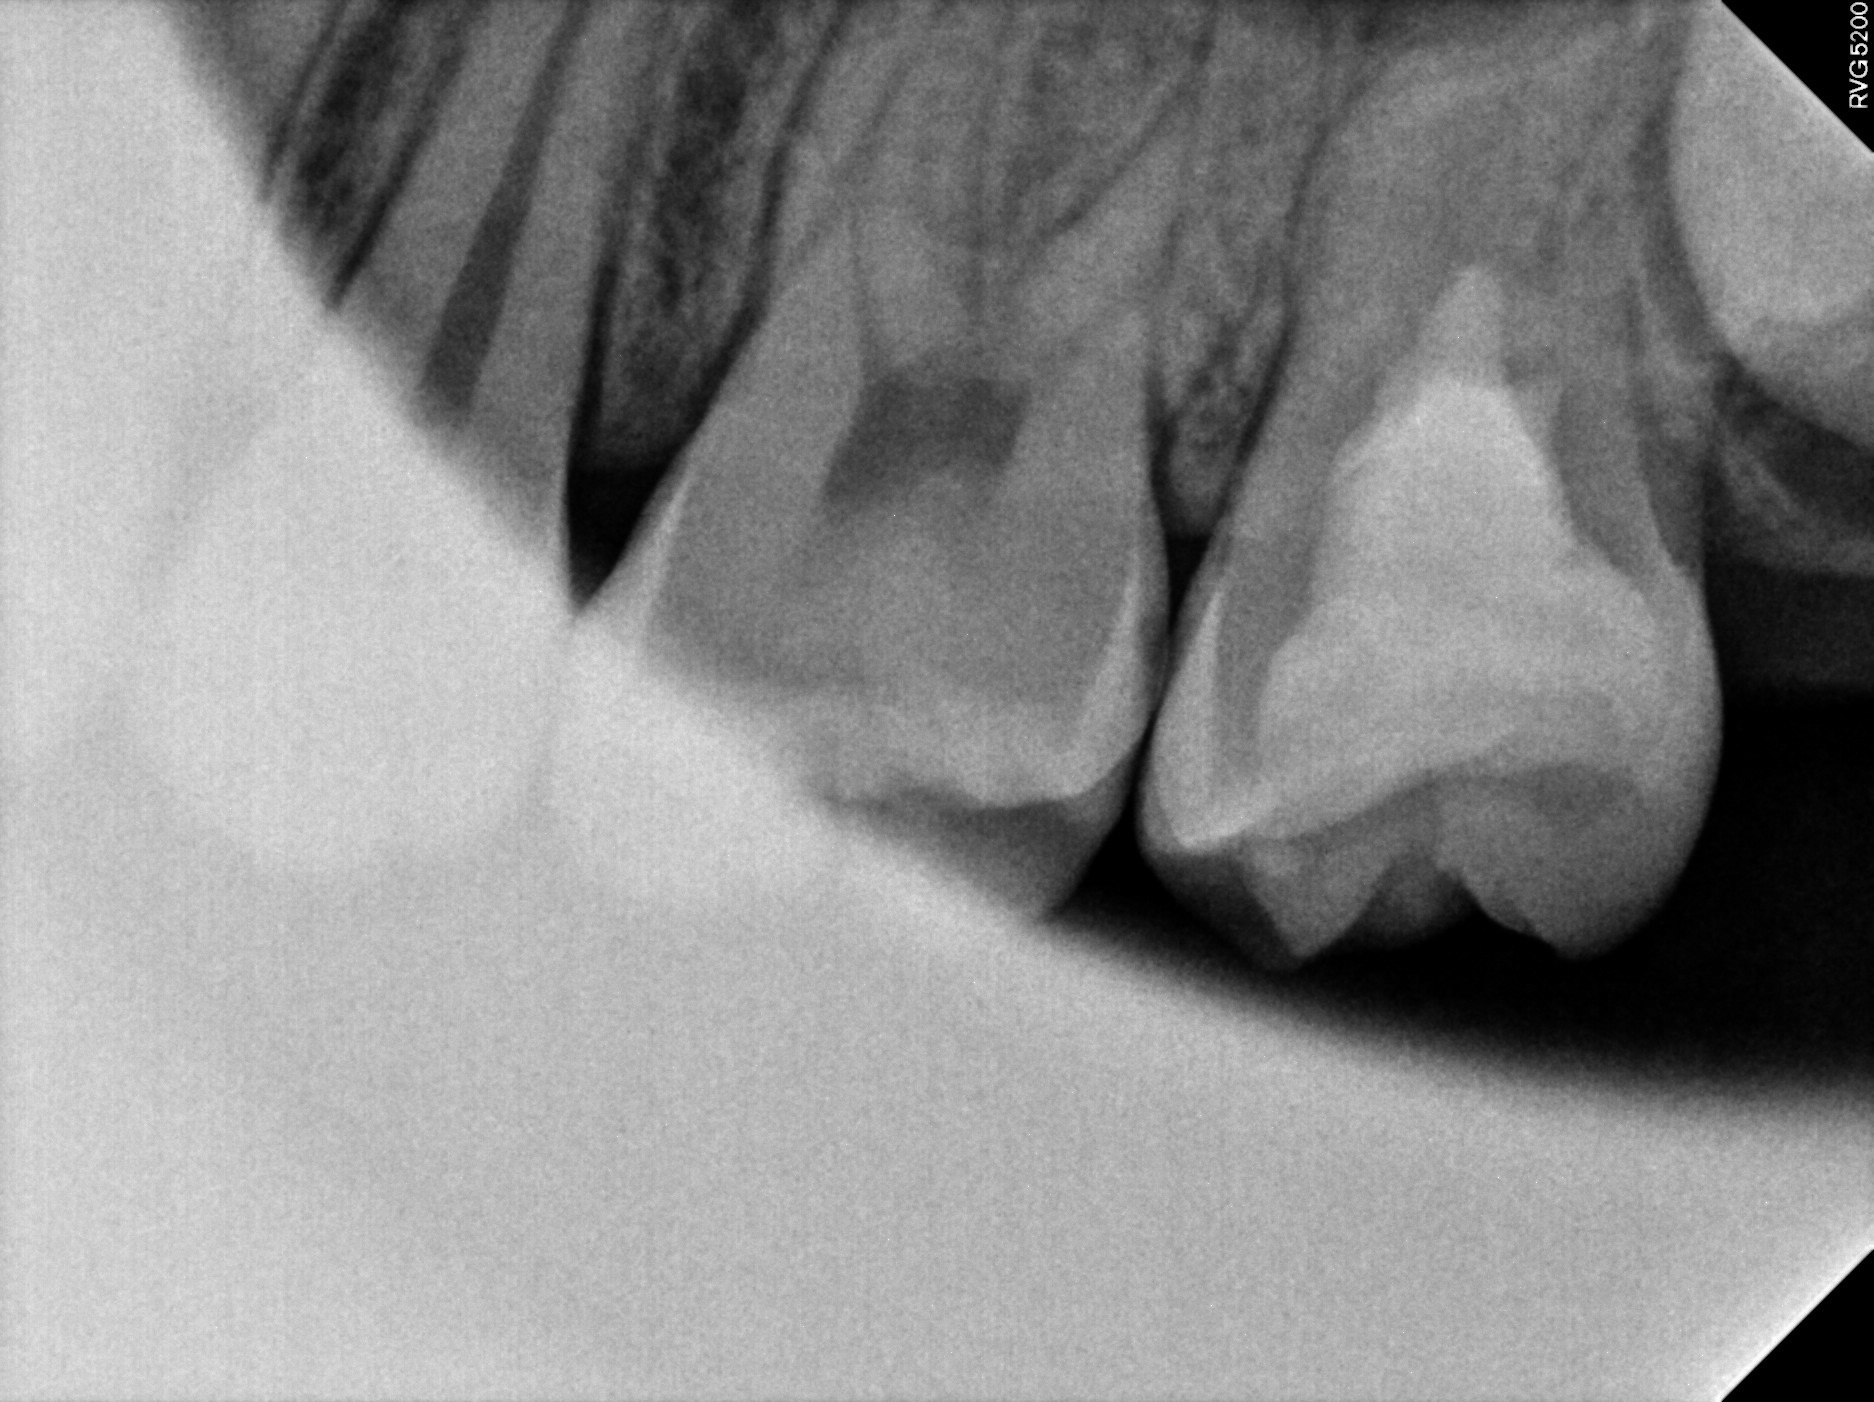

맨 끝의 치아(제2대구치)를 보면 이미 많이 썩어있네요.

이미 신경까지 충치가 진행되었고 잇몸 아래까지 광범위하게 손상받은 상황입니다.

엑스레이를 보면 치아에 까맣게 구멍이 뚫린 것처럼 보이시죠?

이미 충치가 저 정도로 크게 진행된 상황이었습니다.

치료가 다 끝난 후, 엑스레이 사진입니다.

빈틈없이 신경치료와 레진 빌드업이 완료된 것을 확인 하실 수가 있습니다.

아까 위의 엑스레이와는 완전히 다르죠? ㅎㅎ